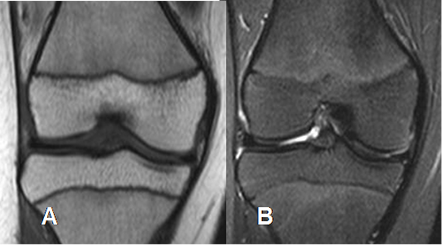

Fig 5. Medula ósea roja normal en adulto.

A: RM sagital en T1 y B: RM sagital en T2. Medula roja con señal intermedia en ambas secuencias.